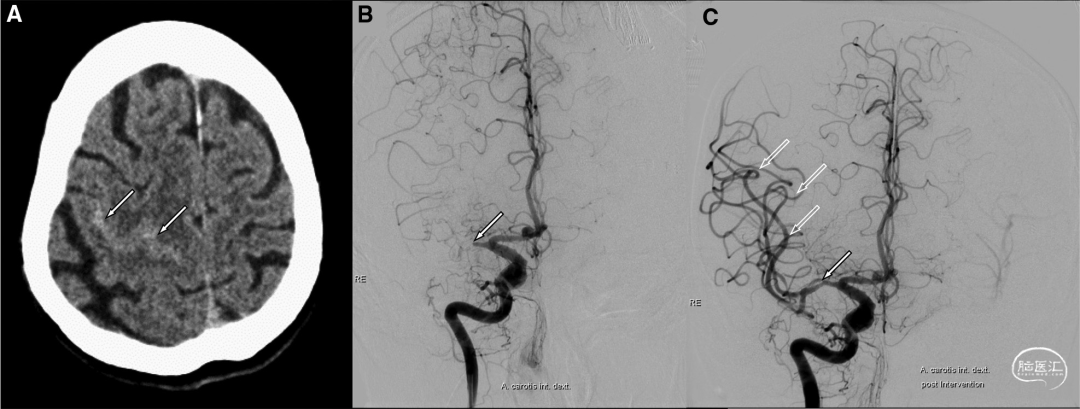

发病2小时CT显示右额凸面蛛网膜下腔出血(图1A)。CTA显示右侧大脑中动脉主干闭塞。随后,机械血栓切除术的治疗成功(图1B和1C)。